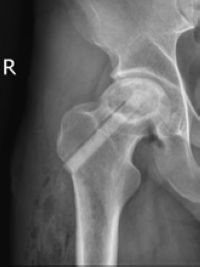

经讨论,决定采用“钻孔减压+陶瓷骨棒支撑治疗”股骨头缺血坏死,即在彻底清理死骨的基础上,在坏死区域植入生长颗粒,“多孔生物陶瓷棒”支撑和引导血管长入的作用,以期望重建骨坏死血供,最终植入的陶瓷棒被自体骨逐渐成骨替换,待自体骨替代后最终实现永久性生物支撑。

郝琦副教授解释说:“陶瓷骨棒植入技术为股骨头缺血坏死提供一种新的微创保髋方法,特别是对于年轻患者更具优势,同时不影响后期关节置换。”

经过治疗后,小段髋部疼痛明显好转,术后3个月复查,已经没有了疼痛症状,能正常行走了。